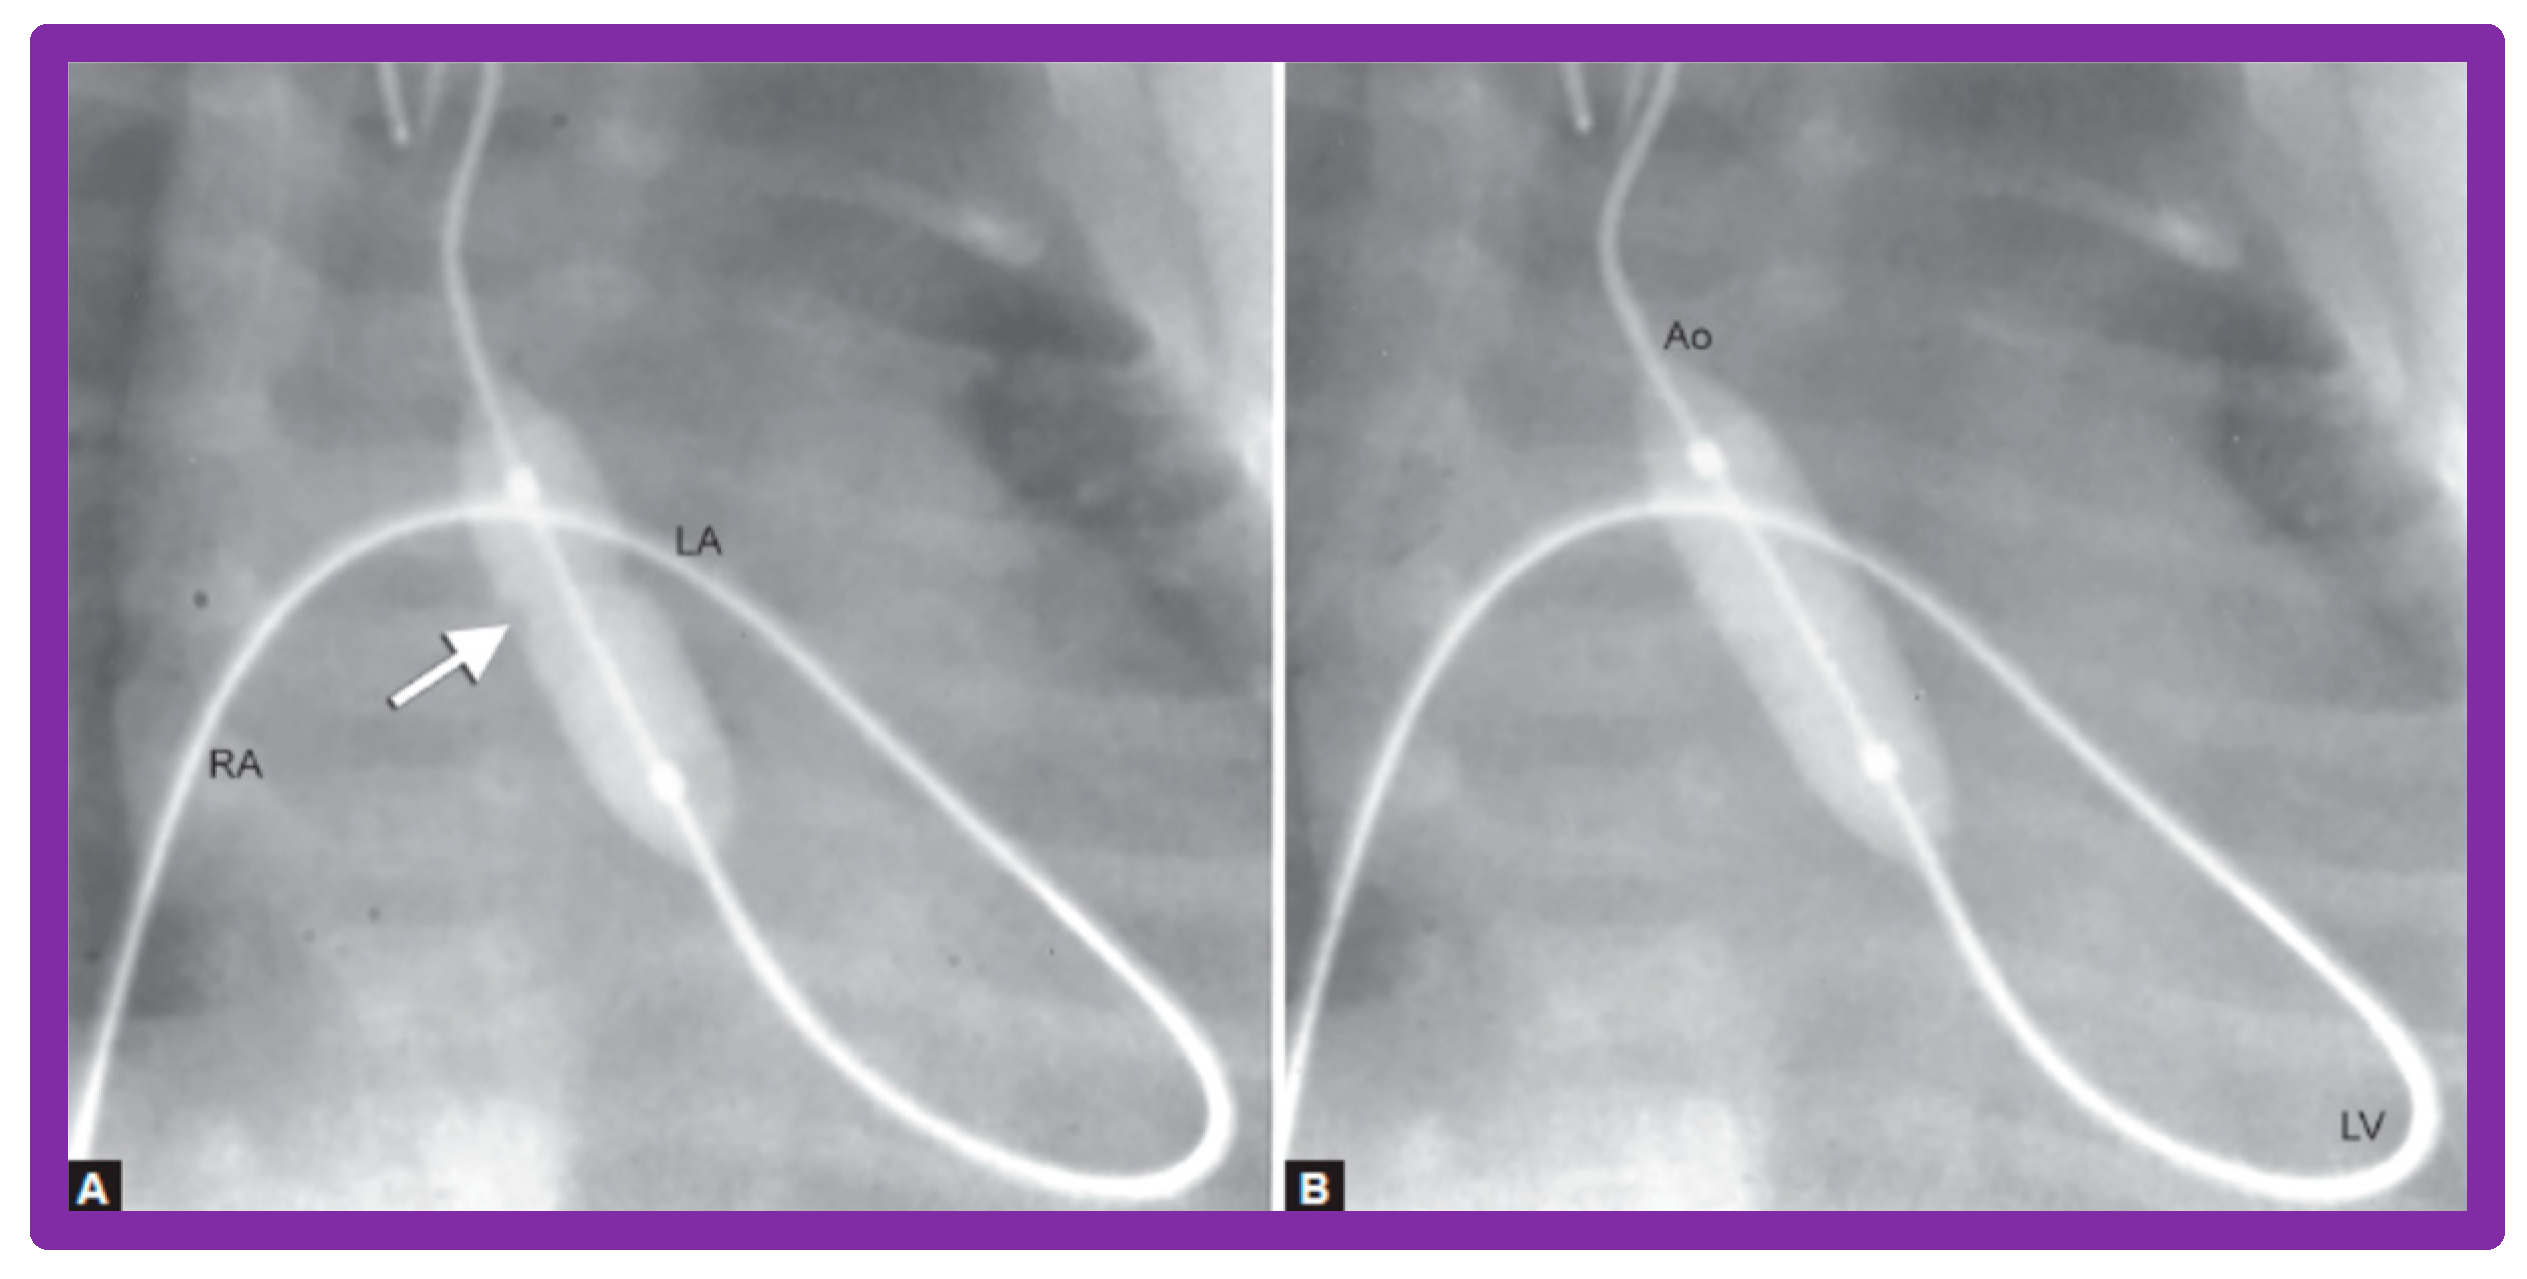

A #4-F multipurpose catheter (Cordis) or a similar catheter is placed in the UV sheath and pushed forward into the left atrium via the PFO and then through the mitral valve into the LV. With the help of a J-shaped and/or a straight, soft-tipped 0.035" Benston guide wires (Cook), the catheter is positioned in the ascending aorta and if possible, the tip of the catheter is negotiated into the proximal descending aorta. At this point, the guidewire is switched with a 0.018" or 0.021" J-tipped guidewire, suitable to accept the chosen balloon valvuloplasty catheter. The multipurpose catheter is withdrawn and a 6 to 8 mm diameter Tyshak II (Braun) or ultrathin (Meditech) balloon dilatation catheter is threaded over the guidewire from the UV, inferior vena cava, right atrium, left atrium, LV, and aorta. During this process, a wide loop of the guidewire in the LV should be maintained. The diameter of the balloon used for BAV should be 0.8 to 1.0 times the aortic valve annulus. Following placement of the balloon catheter across the aortic valve, the balloon is inflated with diluted contrast material with inflation pressures going up to the manufacturer’s recommendations, or till the waist of the balloon is abolished (Figure 27 and Figure 28). One or two more balloon inflations are performed to ensure adequate BAV.

3.2.1. Additional Procedural Details

In babies in whom the guidewire cannot be positioned in the descending aorta or the BAV catheter cannot be placed across the aortic valve, a gooseneck micro-snare (Microvena, White Bear Lake, MN) may be sited in the descending aorta either via the femoral or umbilical artery. Then the tip of the anterogradely placed guide wire is snared and pulled down into the descending aorta and held in place. Thus, an umbilical venous-to-umbilical/femoral arterial wire “rail” is created (Figure 29). A mild traction on the descending aortic section of the wire rail facilitates placement of the BAV catheter across the aortic valve. It should be remembered that a wide wire loop in the LV should be maintained during this process. After the BAV procedure is finished, the guidewire is let go from the snare and removed. To prevent injury of the intracardiac structures, a catheter is maintained over the entire course of the guidewire during guidewire withdrawal [55].

Subsequently, we have improved the technique with the use regular 0.021″ guide wires (Cook, Bloomington, IN) instead of extra-stiff Amplatz wires (Cook) and Tyshak-II catheters (Braun, Bethlehem, PA) (Figure 30) instead ultrathin balloon valvuoloplasty catheters (Meditech, Natick, MA) [56,58]. Since the use of these changes, it was not necessary to use snare nor to institute a guide wire loop. We also observed less arrhythmia during the BAV procedure, apparently because of employing less stiffer wires and better tracking of the Tyshak-II catheters [56,58].

Figure 27. Selected cine-radiographic frames demonstrating the position of the balloon across the aortic valve, introduced anterogradely. Note the waisting (arrows) of the balloon during the initial phases of balloon inflation (A), which was completely abolished after full inflation of the balloon (B). Reproduced from Reference [56].

Figure 28. Selected cine frames demonstrating the position of the balloon across the aortic valve introduced anterogradely from the umbilical vein, right atrium (RA), left atrium (LA), left ventricle (LV) and aorta (Ao). (A) Note the waist (arrow) of the balloon which was completely abolished after further inflation of the balloon (B). Reproduced from Reference [57].